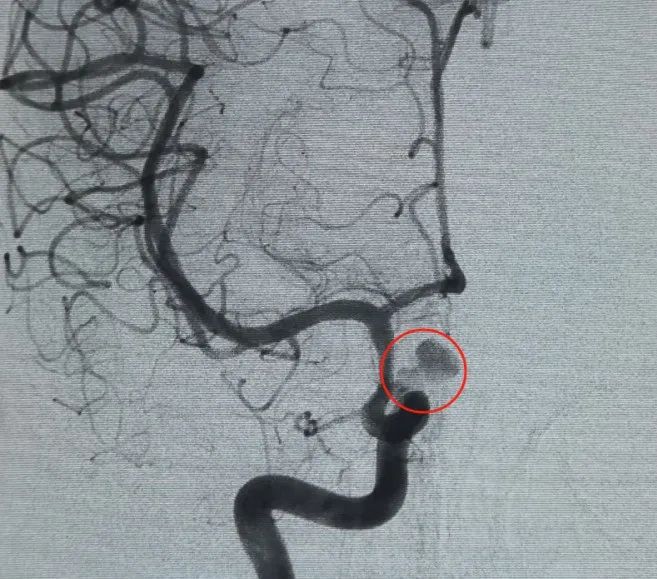

Un Perfiller®3mm × 6 cm bobina expansible y un Perfiller®A continuación se colocaron bobinas expansibles de 3mm x 2 cm para completar la oclusión del cuello. Posteriormente, un Nuva®Se administró un desván de flujo (TJED-D-5.0-16) y se desplegó a través del cuello del aneurisma. La angiografía de seguimiento en las vistas anteroposterior y lateral confirmó una excelente cobertura, buena aposición de la pared y clara radiopacidad, con marcado estancamiento del contraste.

El procedimiento se completó sin problemas, sin complicaciones, y el paciente se recuperó sin déficits neurológicos.